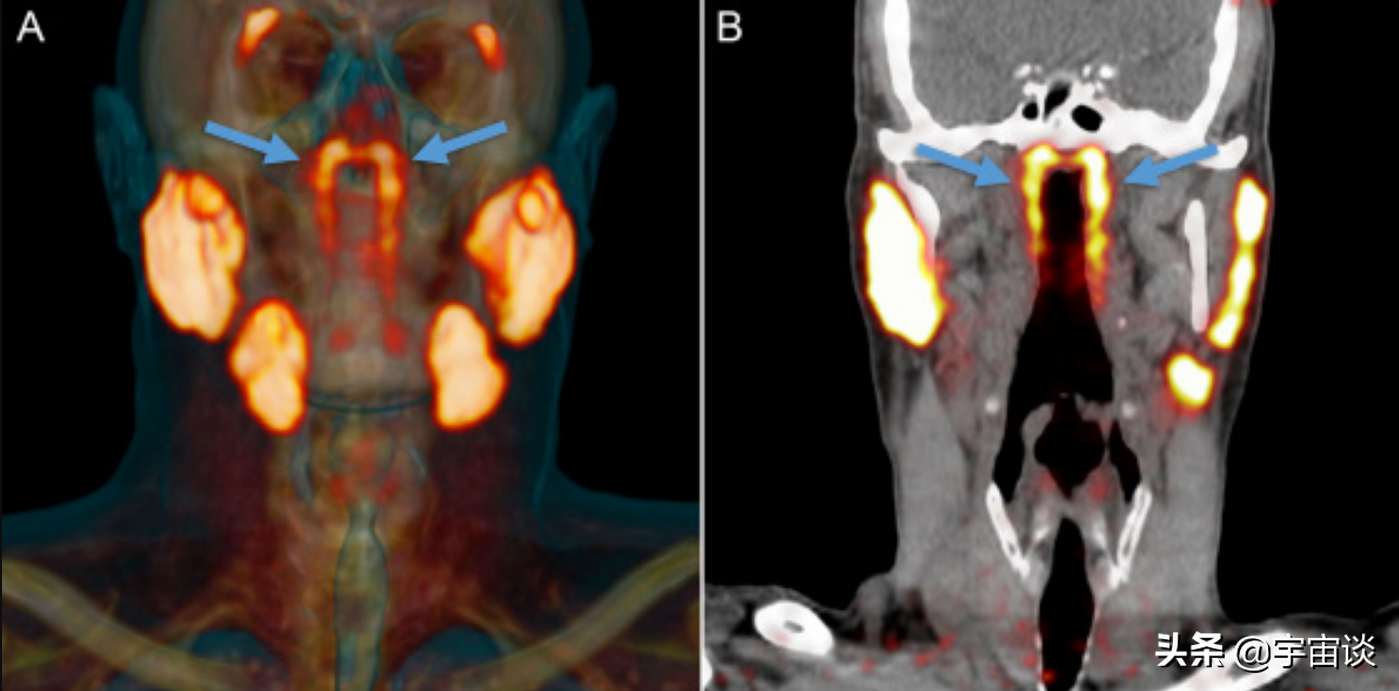

要知道人體是一個非常複雜的生物,構造也十分的複雜,身體內存在著很多細小隱藏比較深的器官沒被我們人類找到是肯定存在的,就在今年的9月份國外的生物家對癌細胞進行研究的時候就無意間發現—在人的鼻子到咽喉深處,有一個之前從未發現的器官,雖然這個器官大小有3.9釐米,但是之前一直沒有被發現,那麼這個器官究竟是什麼呢?

原來科學家發現的這個器官是唾液腺,在此之前人類發現的有三種大唾液腺,分別為腮腺,下頜下腺和舌下腺,不僅如此,還有1000多個小的唾液腺分佈在口腔和喉嚨的黏膜當中。但是從來沒有發現過鼻腔的後方還有一對兒大的,並且對人類非常重要的唾液腺。那麼研究人員是怎麼發現這個新器官的呢?

原來這個研究小組最開始的時候並不是來研究唾液腺和人體結構的,而是研究前列腺癌的,在無意當中發現了這個特殊的器官,並且把它命名為管狀腺。當然發現之後研究小組也隨後對很多人進行了比對,發現這並非是某些人群特有,而是人類都普遍存在的一個器官。這也正是說明了這個器官是人類的標配。而研究小組經過研究後又有了新的發現:這個器官或許對治療癌症有著很大的幫助,尤其是對於一些頭頸部有癌症的患者來說。這又是怎麼一回事呢?